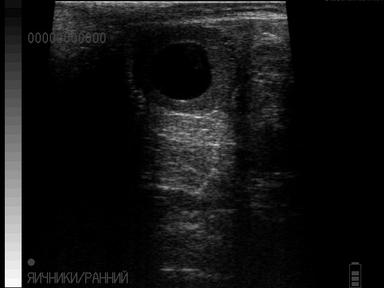

Первоначальное появление кист не проявляется расстройством полового цикла, болезнь часто диагностируется без клинических признаков. Ректальное исследование - наиболее распространенный и точный метод диагностики кист яичников, однако пальпацией отличить лютеиновую кисту от других видов кист достаточно сложно (киста желтого тела). Лютеиновая киста более плотная по консистенции, но это обобщенное показание. Более точной диагностикой является ректальное ультразвуковое исследование, которое дает возможность визуализировать структуры яичника, и различать лютеиновые кисты от других видов кист. При таких аномалиях необходимо своевременно начать лечение, чтобы не допустить экономические потери.